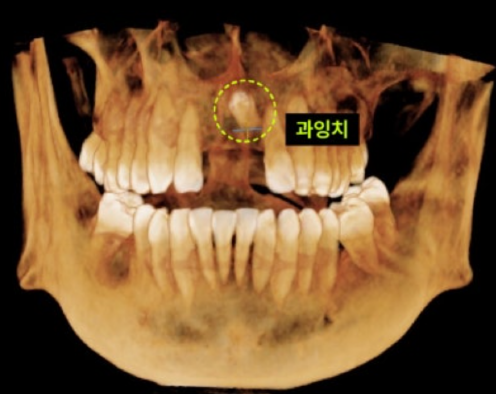

CASE. 30대 남성 환자, "앞니 임플란트 하고 싶어요!" 30대 남성 환자분이 앞니 임플란트 시술을 위해 내원하셨지만, CT촬영 결과 예상치 못한 매복 과잉치가 발견되었습니다. 이는 정상 치아 외에 추가로 자란 불필요한 치아로, 발견 즉시 치료하는 것이 중요합니다. 과잉치, 왜 치료해야 할까?  과잉치는 다양한 문제를 일으킬 수 있어 발치가 필요합니다.

이백점치과의 정밀 진단 환자의 과잉치는 입천장 뼈 속에 거꾸로 누워있었고, 중요한 신경과 혈관이 지나는 '비구개관(Incisive Canal)'을 침범한 상태였습니다. 이처럼 민감한 부위의 매복 과잉치를 제거할 때는 비구개신경 손상이나 출혈에 각별히 주의해야 합니다. 이백점치과는 최신 장비를 활용한 정밀 진단으로 이런 디테일까지 놓치지 않습니다.